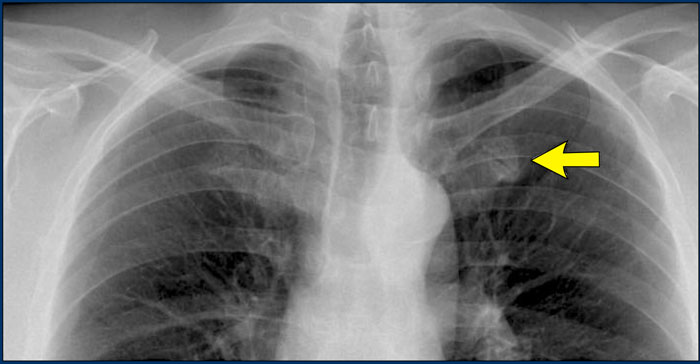

Hidden area (5): Mass Behind the First Rib

In some patients, an accessory joint at the anterior aspect of the first rib may simulate a mass, as we learned earlier.

However this area is also a "hidden zone", where true lesions can be masked.

• In this case, a small lung carcinoma was obscured by the left first rib on the PA view.

• On the lateral film, the lesion is visible in the retrosternal space.

Continue with the PET-CT...

Subsequent PET-CT imaging confirmed a hypermetabolic tumor (arrow), with metastases to the bone and liver.

• Diagnosis was confirmed via biopsy of an osteolytic metastasis in the iliac bone.